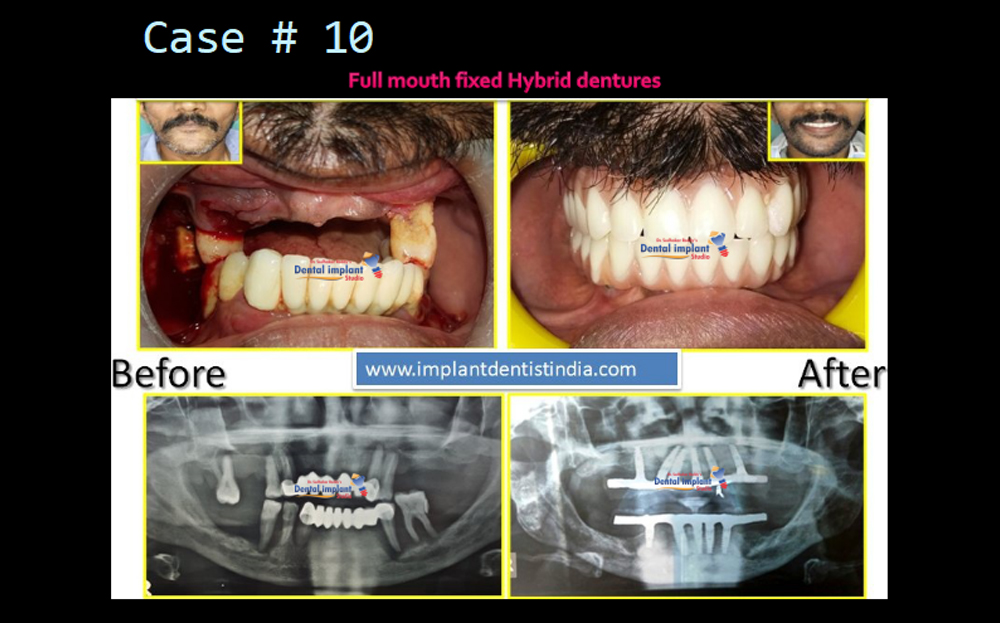

Full Fixed Dentures (Hybrid Dentures) | View Case Series